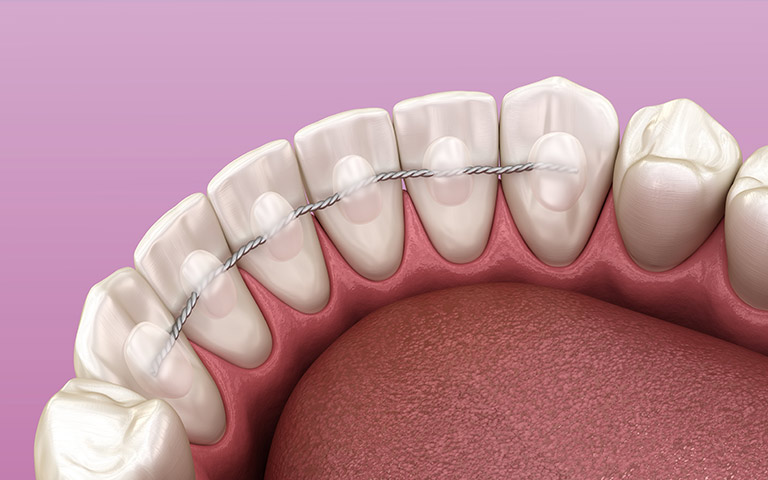

Para terminar nuestro tratamiento, y como siempre, se le dispuso un retenedor fijo y uno removible en ambas arcadas para garantizar la estabilidad del tratamiento y las revisiones periódicas.